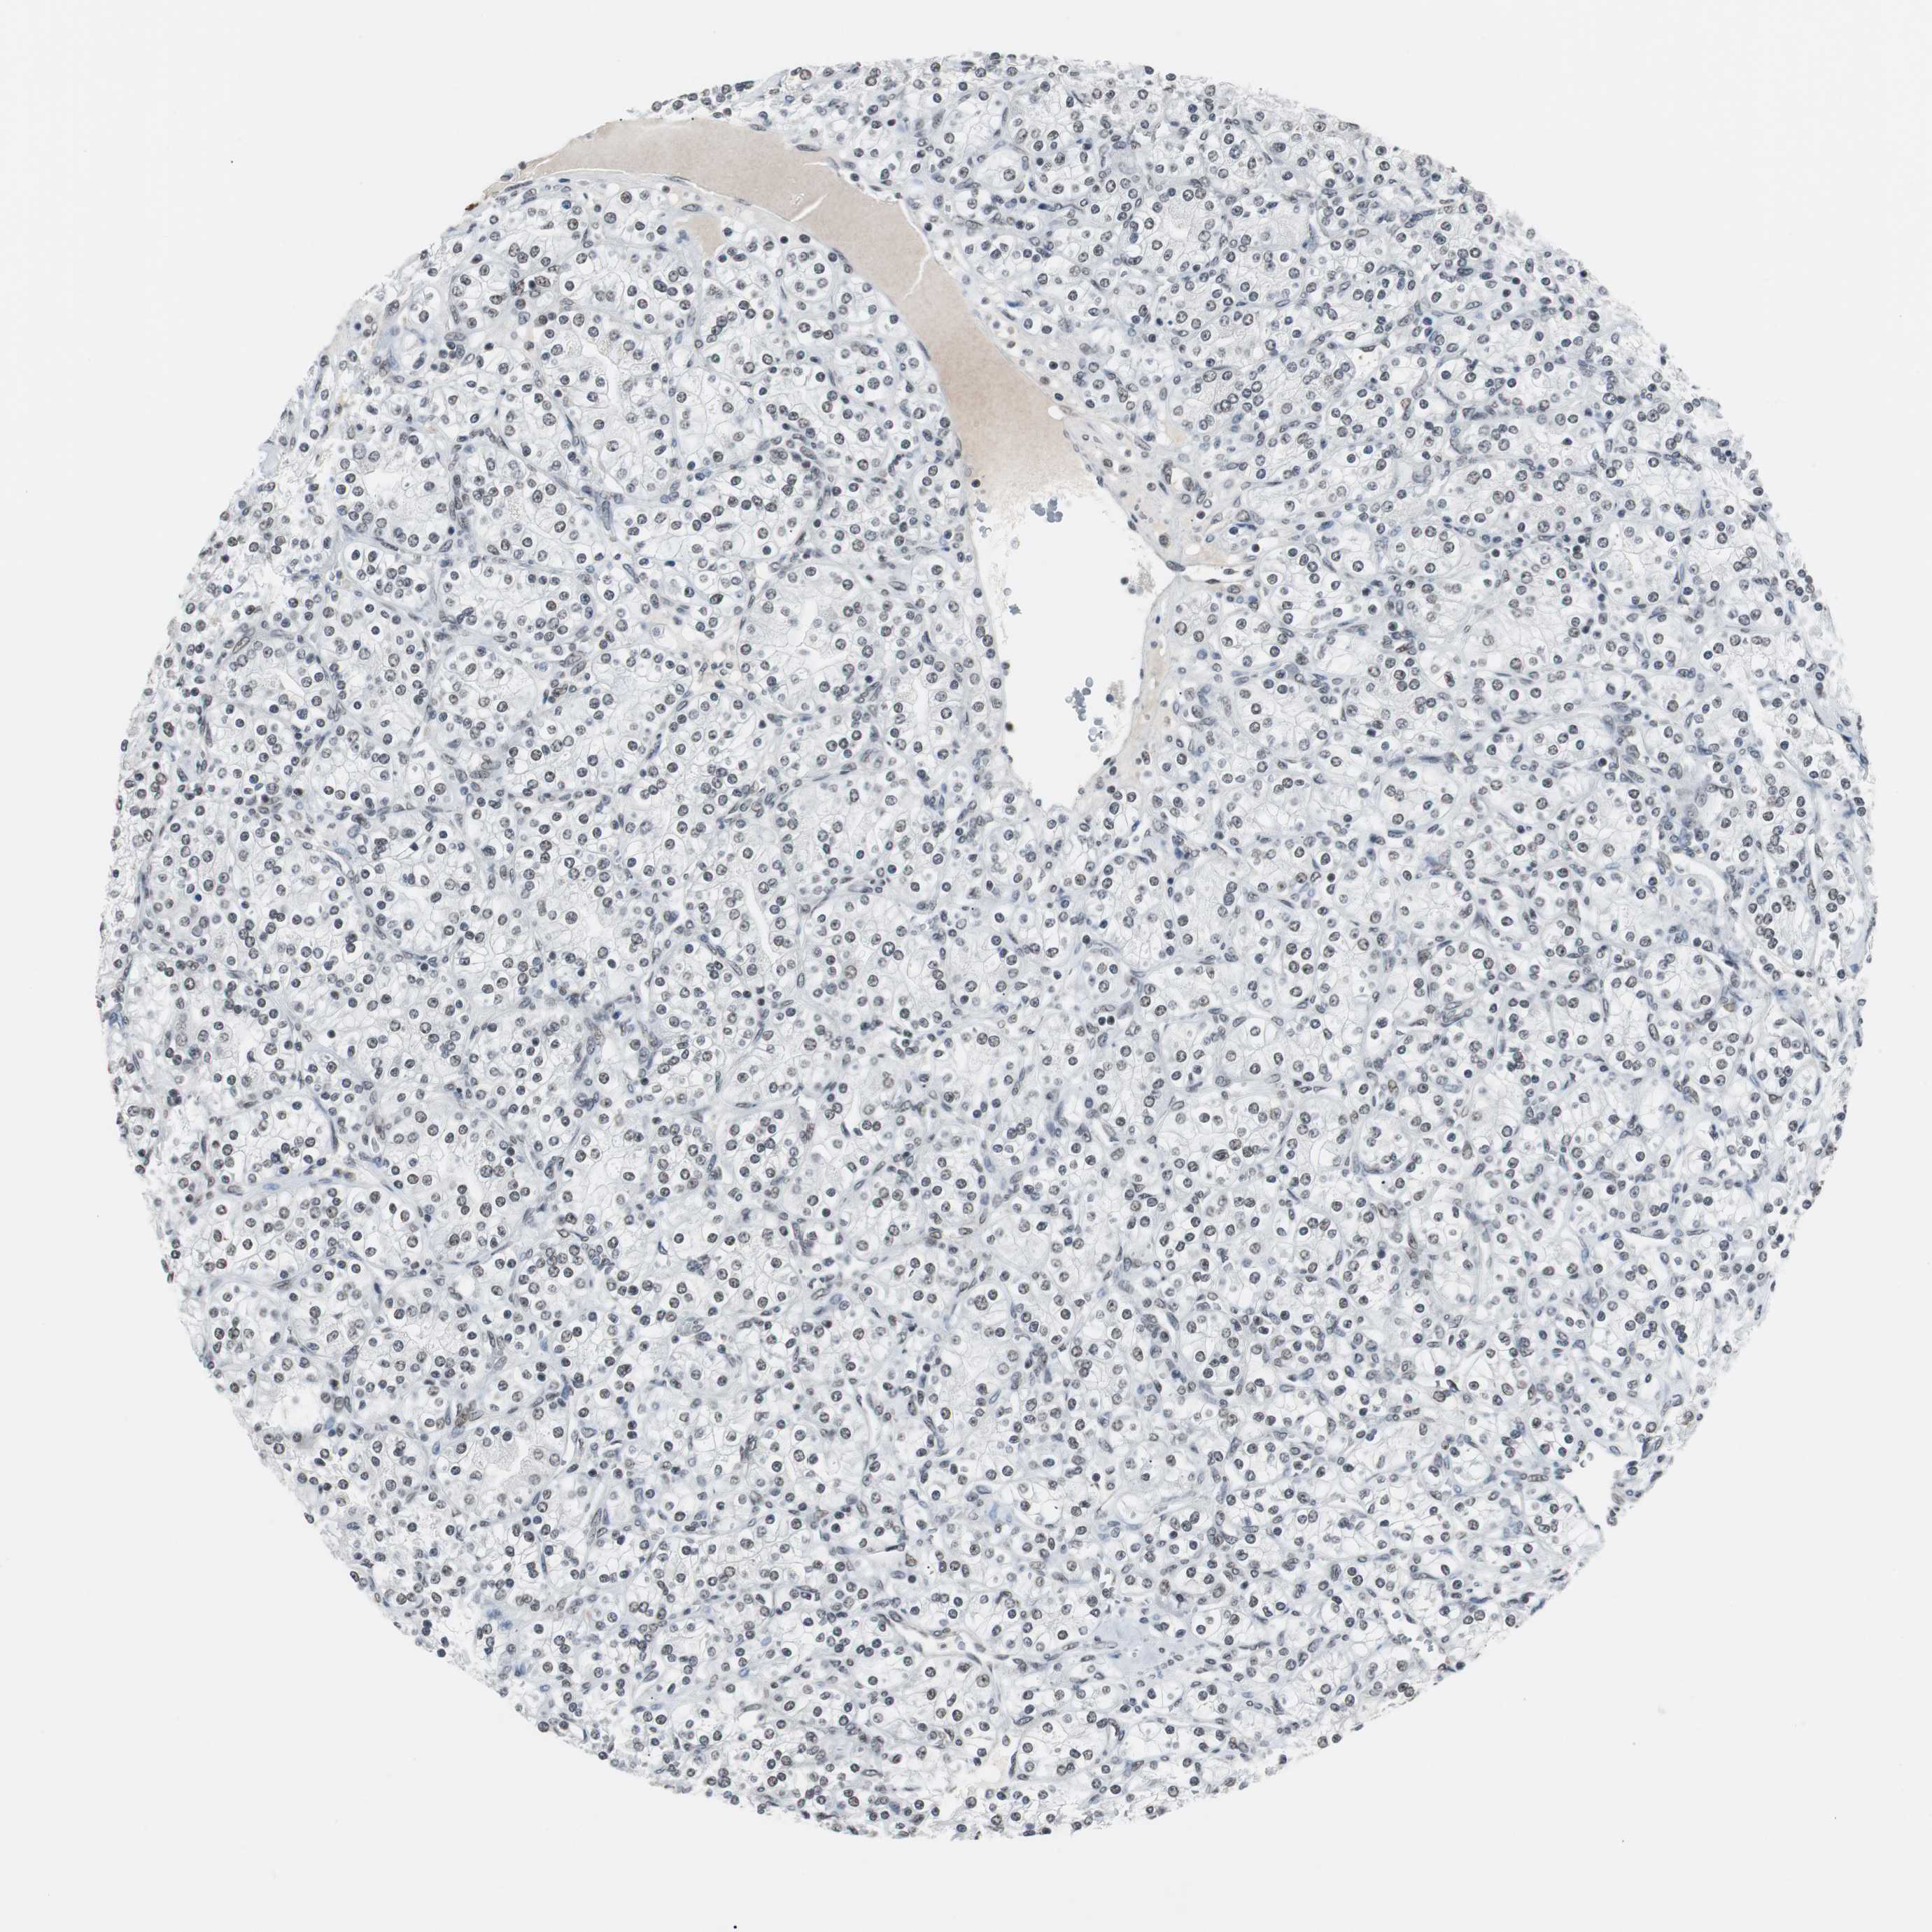

KIDNEY RENAL CLEAR CELL CARCINOMA (VALIDATION) - Interactive survival scatter ploti

The Survival Scatter plot shows the clinical status (i.e. dead or alive) for all individuals in the patient cohort, based on the same data that underlies the corresponding Kaplan-Meier plots. Patients that are alive at last time for follow-up are shown in blue and patients who have died during the study are shown in red.

The x-axis shows the expression levels (FPKM) of the investigated gene in the tumor tissue at the time of diagnosis. The y-axis shows the follow-up time after diagnosis (years). Both axes are complimented with kernel density curves demonstrating the data density over the axes. The top density plot shows the expression levels (FPKM) distribution among dead (red) and alive patients (blue). The right density plot shows the data density of the survived years of dead patients with high and low expression levels respectively, stratified using the cutoff indicated by the vertical dashed line through the Survival Scatter plot. This cutoff is automatically defined based on the FPKM cutoff that minimizes the p-score. The cutoff can be changed by dragging the vertical line or by entering a cutoff value in the square labeled "Current cut-off".

Under the Survival Scatter plot the p-score landscape (black curve; left axis) is shown together with dead median separation (red curve; right axis). Dead median separation is the difference in median mRNA expression between patients who have died with high and low expression, respectively. It is calculated as follows: median FPKM expression of dead patients with high expression - median FPKM expression of dead patients with low expression. This is intended to aid the user in visually exploring custom cutoffs and the associated p-scores and dead median separation.

Individual patient data is displayed and can be filtered by clicking on one or more of the category buttons on the top of the page. Categories describing expression level and patient information include: high, low, alive, dead, female, male and tumor stages. The scale of the x-axis can be toggled between linear and log-scale by clicking on the "x log" button. Mouse-over function shows TCGA ID, patient information and mRNA expression (FPKM) for each patient.

& Survival analysisi

Kaplan-Meier plots summarize results from analysis of correlation between mRNA expression level and patient survival. Patients were divided based on level of expression into one of the two groups "low" (under cut off) or "high" (over cut off). X-axis shows time for survival (years) and y-axis shows the probability of survival, where 1.0 corresponds to 100 percent.

TAF7 is not prognostic in Kidney Renal Clear Cell Carcinoma (validation)

Best expression cut offi

Based on the FPKM value of each gene, patients were classified into two groups and association between prognosis (survival) and gene expression (FPKM) was examined. The best expression cut-off refers the FPKM value that yields maximal difference with regard to survival between the two groups at the lowest log-rank P-value. Best expression cut-off was selected based on survival analysis .

When clicking on this number, the vertical dashed line indicating cut-off, the interactive survival plot, and the Kaplan-Meier curve will be adjusted to show results based on the best expression cut-off.

: 95.08

P scorei

Log-rank P value for Kaplan-Meier plot showing results from analysis of correlation between mRNA expression level and patient survival.

N/A

TCGA RNA samplesi

RNA-seq data is reported as average FPKM (number Fragments Per Kilobase of exon per Million reads), generated by the The Cancer Genome Atlas (TCGA) .

Normal distribution across the dataset is visualized with box plots, shown as median and 25th and 75th percentiles. Points are displayed as outliers if they are above or below 1.5 times the interquartile range. FPKM values of the individual samples are presented next to the box plot.

Average pTPM 106.3

Number of samples 100